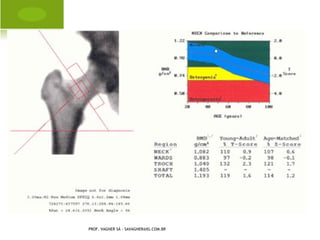

D ENSITOMETRIA Ó SSEA

PROF. VAGNER SÁ - SAVAGNER@IG.COM.BR